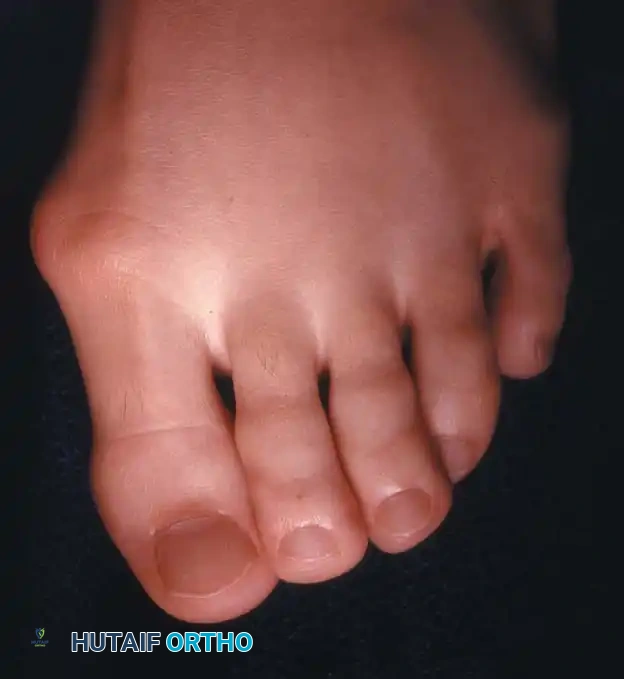

Hallux valgus (lateral deviation of the great toe) is not a single disorder, as the name implies, but a complex deformity of the fi rst ray that frequently is accompanied by deformity and symptoms in the lesser toes (Fig. 78-1). Often the angle between the fi rst and second metatarsals is more than the 8 to 9 degrees usually considered to be the upper limits of normal. The valgus angle of the fi rst metatarsophalangeal joint also is more than the 15 to 20 degrees considered to be the upper limits of normal (Fig. 78-2). If the valgus angle of the fi rst metatarsophalangeal joint exceeds 30 to 35 degrees, pronation of the great toe usually results. With this abnormal rotation, the abductor hallucis, which is normally plantar to the fl exion-extension axis of the fi rst metatarsophalangeal joint, moves further plantarward (Fig. 78-3). In this case, the only restraining medial structure is the medial capsular ligament with its capsulosesamoid portion (inserting into the base of the proximal phalanx) (Fig. 78-4) and capsulophalangeal portion (inserting into the plantar plate). The adductor hallucis, which is unopposed by the abductor hallucis, pulls the great toe further into valgus, stretching the medial capsular ligament (particularly the capsulosesamoid), attenuating this structure, and allowing the metatarsal head to drift medially from the sesamoids. In addition, the fl exor hallucis brevis, fl exor hallucis longus, adductor hallucis, and extensor hallucis longus increase the valgus moment at the metatarsophalangeal joint, further deforming the fi rst ray. The deep transverse intermetatarsal ligament runs between the plantar plates at the metatarsophalangeal joints and does not insert into bone on the adjacent sides of the metatarsal heads. Finally, the sesamoid ridge on the plantar surface of the fi rst metatarsal head (the crista) fl attens because of pressure (abutment) from the tibial sesamoid (Fig. 78-5). With this restraint lost, the fi bular sesamoid displaces partially or completely into the fi rst intermetatarsal space (see Fig. 78-2). In this situation, the patient is bearing less weight on the fi rst ray and more on the lesser metatarsal heads, increasing the likelihood of transfer metatarsalgia, callosities, and stress fracture of a lesser metatarsal.

Fig. 78-1 Multiple components of hallux valgus and associated deformities.

a congruent metatarsophalangeal articulation; phalangeal osteotomy or distal metatarsal osteotomy, rather than tightening of the medial capsular repair, should be used for further correction. The valgus posture of the great toe frequently causes a hammer toe–like deformity of the second toe (Fig. 78-7). In addition, the splaying of the forefoot makes the wearing of shoes more diffi cult; with shoes that have a narrow toe box, corns often develop, as does bursal hypertrophy over the medial eminence of the fi rst metatarsal head (bunion). With valgus subluxation of the fi rst metatarsophalangeal joint, osteoarthritis frequently develops. In this case, the entire spectrum of hallux valgus is present: varus deformity of the fi rst metatarsal, valgus of the great toe, bunion formation, arthritis of the fi rst metatarsophalangeal joint, hammer toe of one or more toes, corns, calluses, and meta-